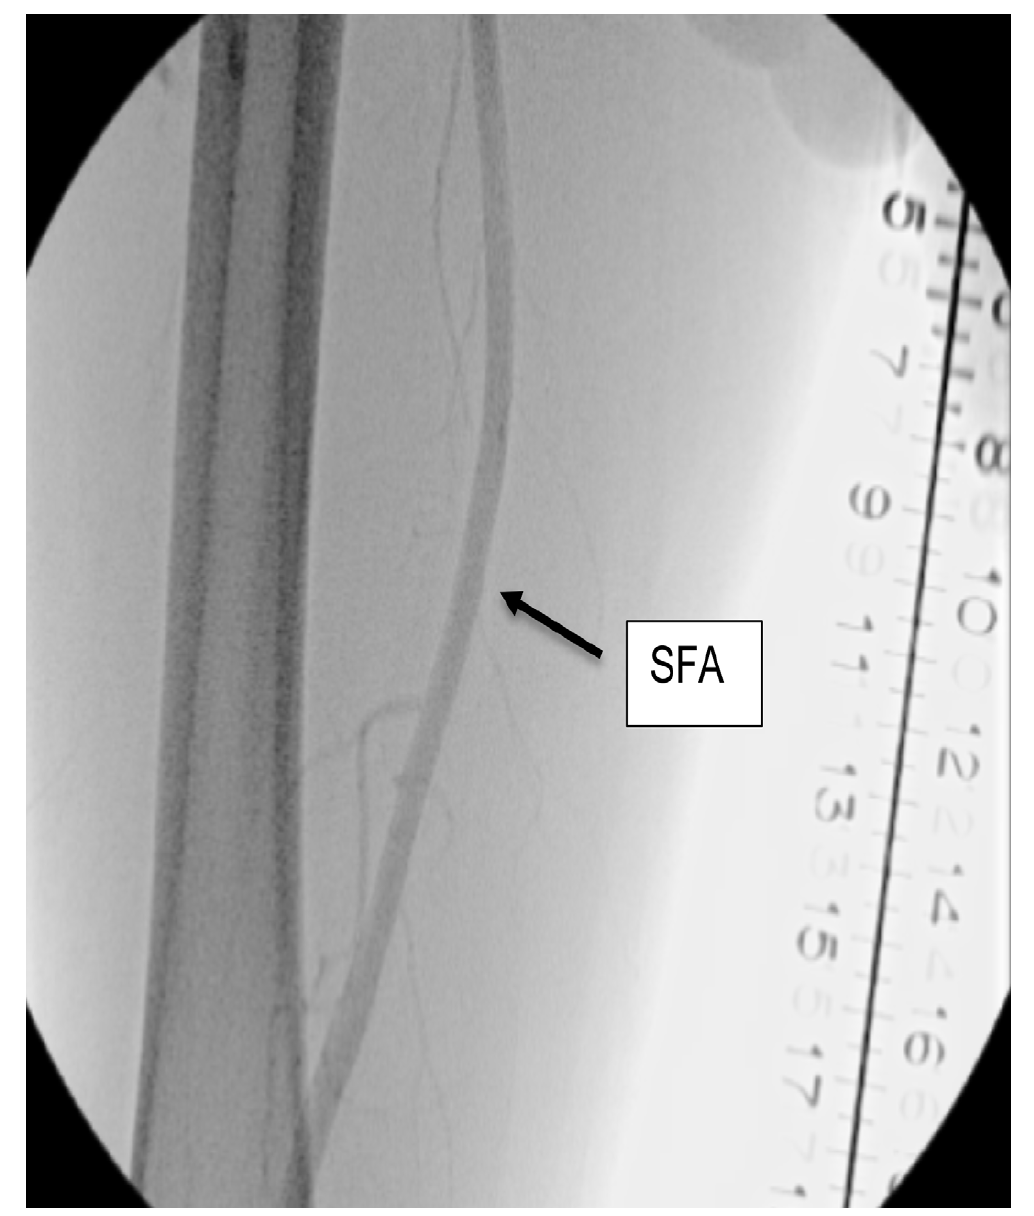

A right lower-extremity angiogram was performed using ultrasound guidance for antegrade access of the proximal superficial femoral artery (Figure 2A). Fluoroscopic acquisition demonstrated no significant disease in the superficial femoral artery (Figure 2B) and popliteal artery (Figure 2C), with no significant stenosis seen in the anterior tibial artery, PTA, and peroneal artery (Figure 2D). Pedal angiography demonstrated a complete pedal-plantar loop formed by the DPA and the lateral plantar artery (LPA) (Figure 2F).